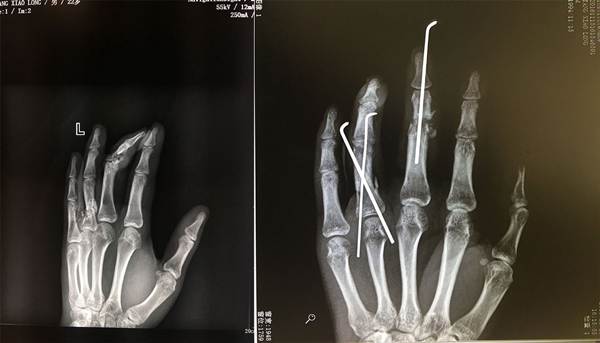

On the morning of Oct. 14, Tang’s middle and index fingers were caught in a rotating machine. The middle finger was almost severed, and its bones were crushed. An initial examination revealed that the finger's nerves and arteries were severely damaged.

After several discussions, doctors decided to try their best to save the young man's fingers. Dr. Li Yong performed Tang's surgery, which lasted four hours. After the surgery, Tang’s pale fingertips became red again, indicating that the operation was successful.

“After the operation, my fingers were fragile, like newly planted trees. The hospital offered me the best and most modern care. They even opened a high-press oxygen cabin for me, which is usually only opened for 16 patients," Tang described in a thank-you letter to the hospital's staff.

Tang was discharged from the hospital on Oct. 31. After more than one month of treatment, his fingers have resumed normal function.